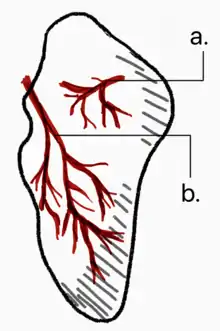

Avascular necrosis (AVN) is one complication of scaphoid fracture. Since the scaphoid receives its arterial supply in a retrograde fashion (i.e. from distal to proximal pole), the part proximal to the fracture is usually affected.[5]

Risk of AVN depends on the location of the fracture.

- Fractures in the proximal third have a high incidence of AVN (~30%)

- Waist fractures in the middle third is the most frequent fracture site and has moderate risk of AVN.

- Fractures in the distal third are rarely complicated by AVN.

Non union can also occur from undiagnosed or undertreated scaphoid fractures. Arterial flow to the scaphoid enters via the distal pole and travels to the proximal pole. This blood supply is tenuous, increasing the risk of nonunion, particularly with fractures at the wrist and proximal end.[4] If not treated correctly non-union of the scaphoid fracture can lead to wrist osteoarthritis.

Fractures that are more proximal take longer to heal. It is expected the distal third will heal in 6 to 8 weeks, the middle third will take 8–12 weeks, and the proximal third will take 12–24 weeks.[7][8] The Scaphoid receives its blood supply primarily from lateral and distal branches of the radial artery. Blood flows from the top/distal end of the bone in a retrograde fashion down to the proximal pole; if this blood flow is disrupted by a fracture, the bone may not heal. Surgery is necessary at this point to mechanically mend the bone together.